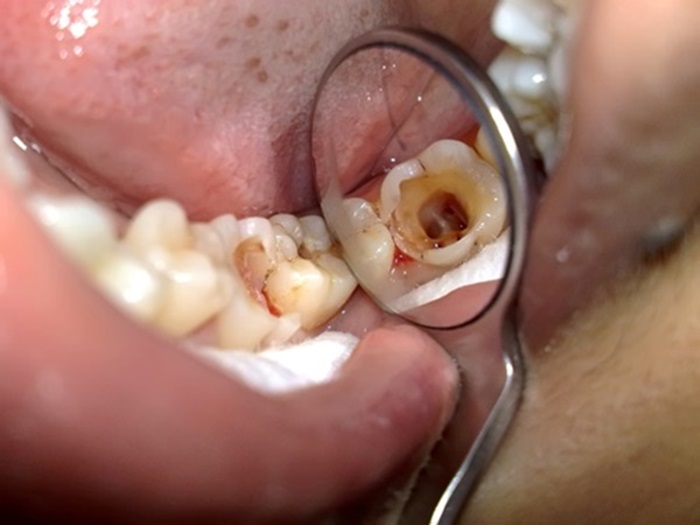

Răng số 7 sâu vỡ có nên nhổ bỏ không và sau khi nhổ bỏ có cần trồng lại không là câu hỏi mà chúng tôi nhận được rất nhiều trong quá trình tư vấn cho khách hàng. Những chiếc răng hàm sâu vỡ mang lại những cảm giác đau khó chịu kéo dài mà uống thuốc cũng không có nhiều tác dụng. Vậy phải làm gì khi gặp vấn đề đó thì chúng ta cùng theo dõi bài viết dưới đây.